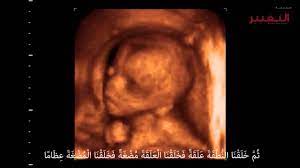

شكل الجنين في الشهر السادس بالسونار حجم الجنين خلال اشهر الحمل افضل جديد